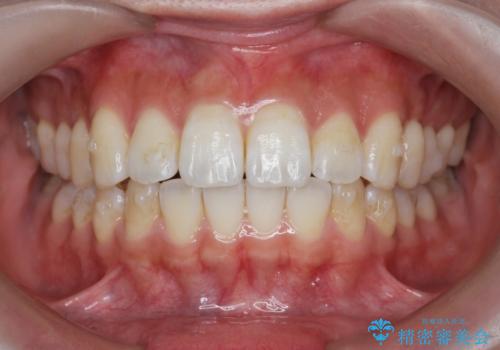

- 前歯の噛み合わせの開きの改善を求めて来院されました。

奥歯はほとんど動かさず(奥歯の噛み合わせはほとんど変えず)前歯のIPR矯正でガタつき前突感(出っ歯感)の改善を計画します。

ほとんど前歯のみの矯正治療であることからトータル14枚のマウスピースで並べるインビザラインライトによる治療を行います。